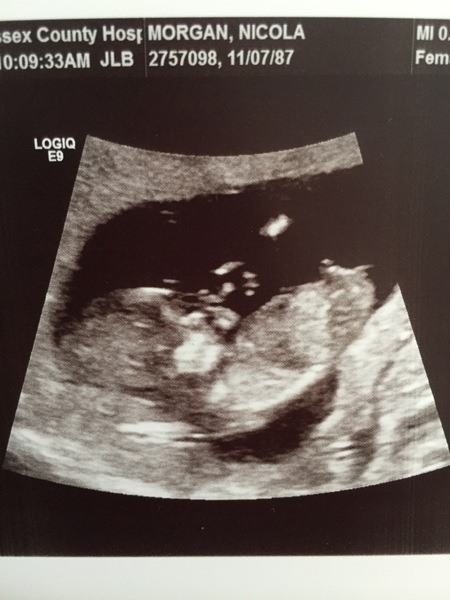

MagicalCreatures · 14/06/2018 12:01

Everything looks good so far.

Feeling very happy right now.

Baby kept turning away from us so was hard to get a good picture. But he/she was kicking and turning like crazy. So amazing to see. Official due date they’ve given me is the 28th December. (My sisters birthday) So 1 day behind but All my other scans have measured to the 27th so in my head it’s still that.

December 2018 Babies - Thread #2

At my 12 week scan they dated me 3 days ahead which now makes me November 28th, I still think I’ll have a December baby though. I love how chilled baby seems to look 😍 and crazy that you can see his/her brain. Loving everyone’s 12 week scans.